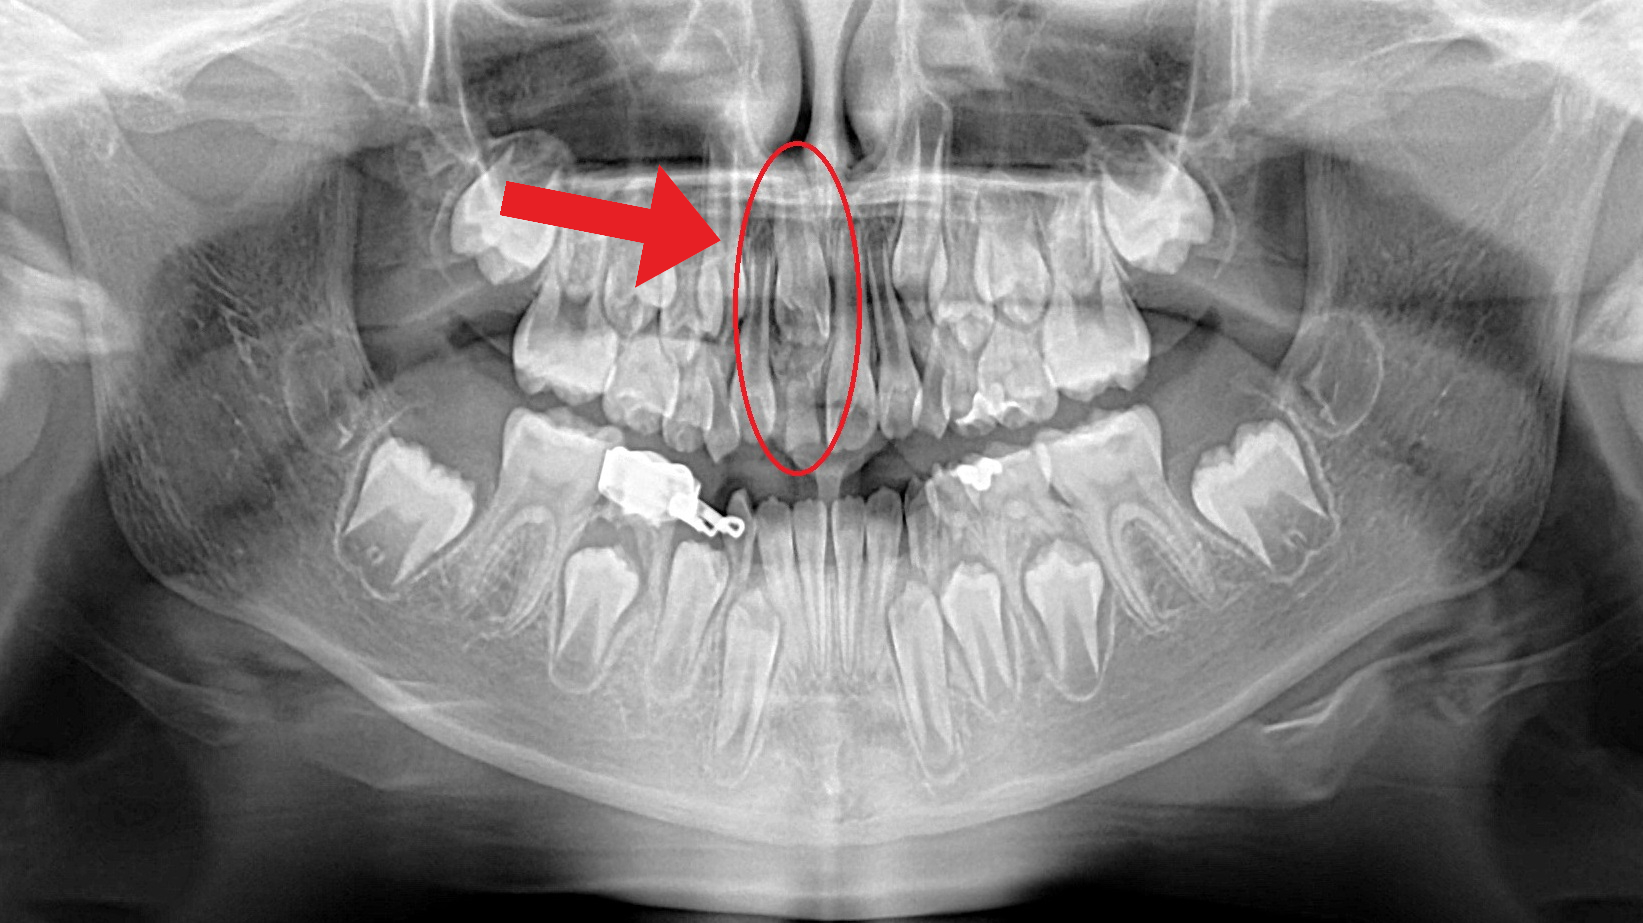

Here is an example of a child that was alerted to some strange tooth eruption, but the problem was already quite severe. Had the child been referred earlier, the problem could have been much less severe

This patient came in because one of her front baby teeth had not fallen out. A panoramic X-ray showed that her permanent front tooth was impacted and stuck high in the jaw shown in the first photo.

While removal was initially recommended, we pursued a more conservative option. By attaching a small orthodontic device, we were able to gently guide the tooth into its proper position. This approach saved her natural front tooth and avoided the need for an implant—something that can never truly replace a natural smile.